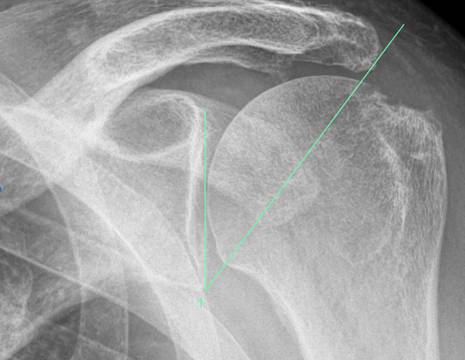

Riguardo invece i fattori legati alla morfologia della spalla, è stato dimostrato che un ACROMION DISCENDENTE, misurato tramite il critical shoulder angle (CSA), come mostrato in Figura 1, aumenta il carico sul tendine del sovraspinato durante l'abduzione della spalla. La riduzione del CSA mediante un'acromioplastica durante l’intervento si è dimostrata sicura e può ridurre il rischio di una nuova lesione dopo un intervento di riparazione della cuffia dei rotatori.